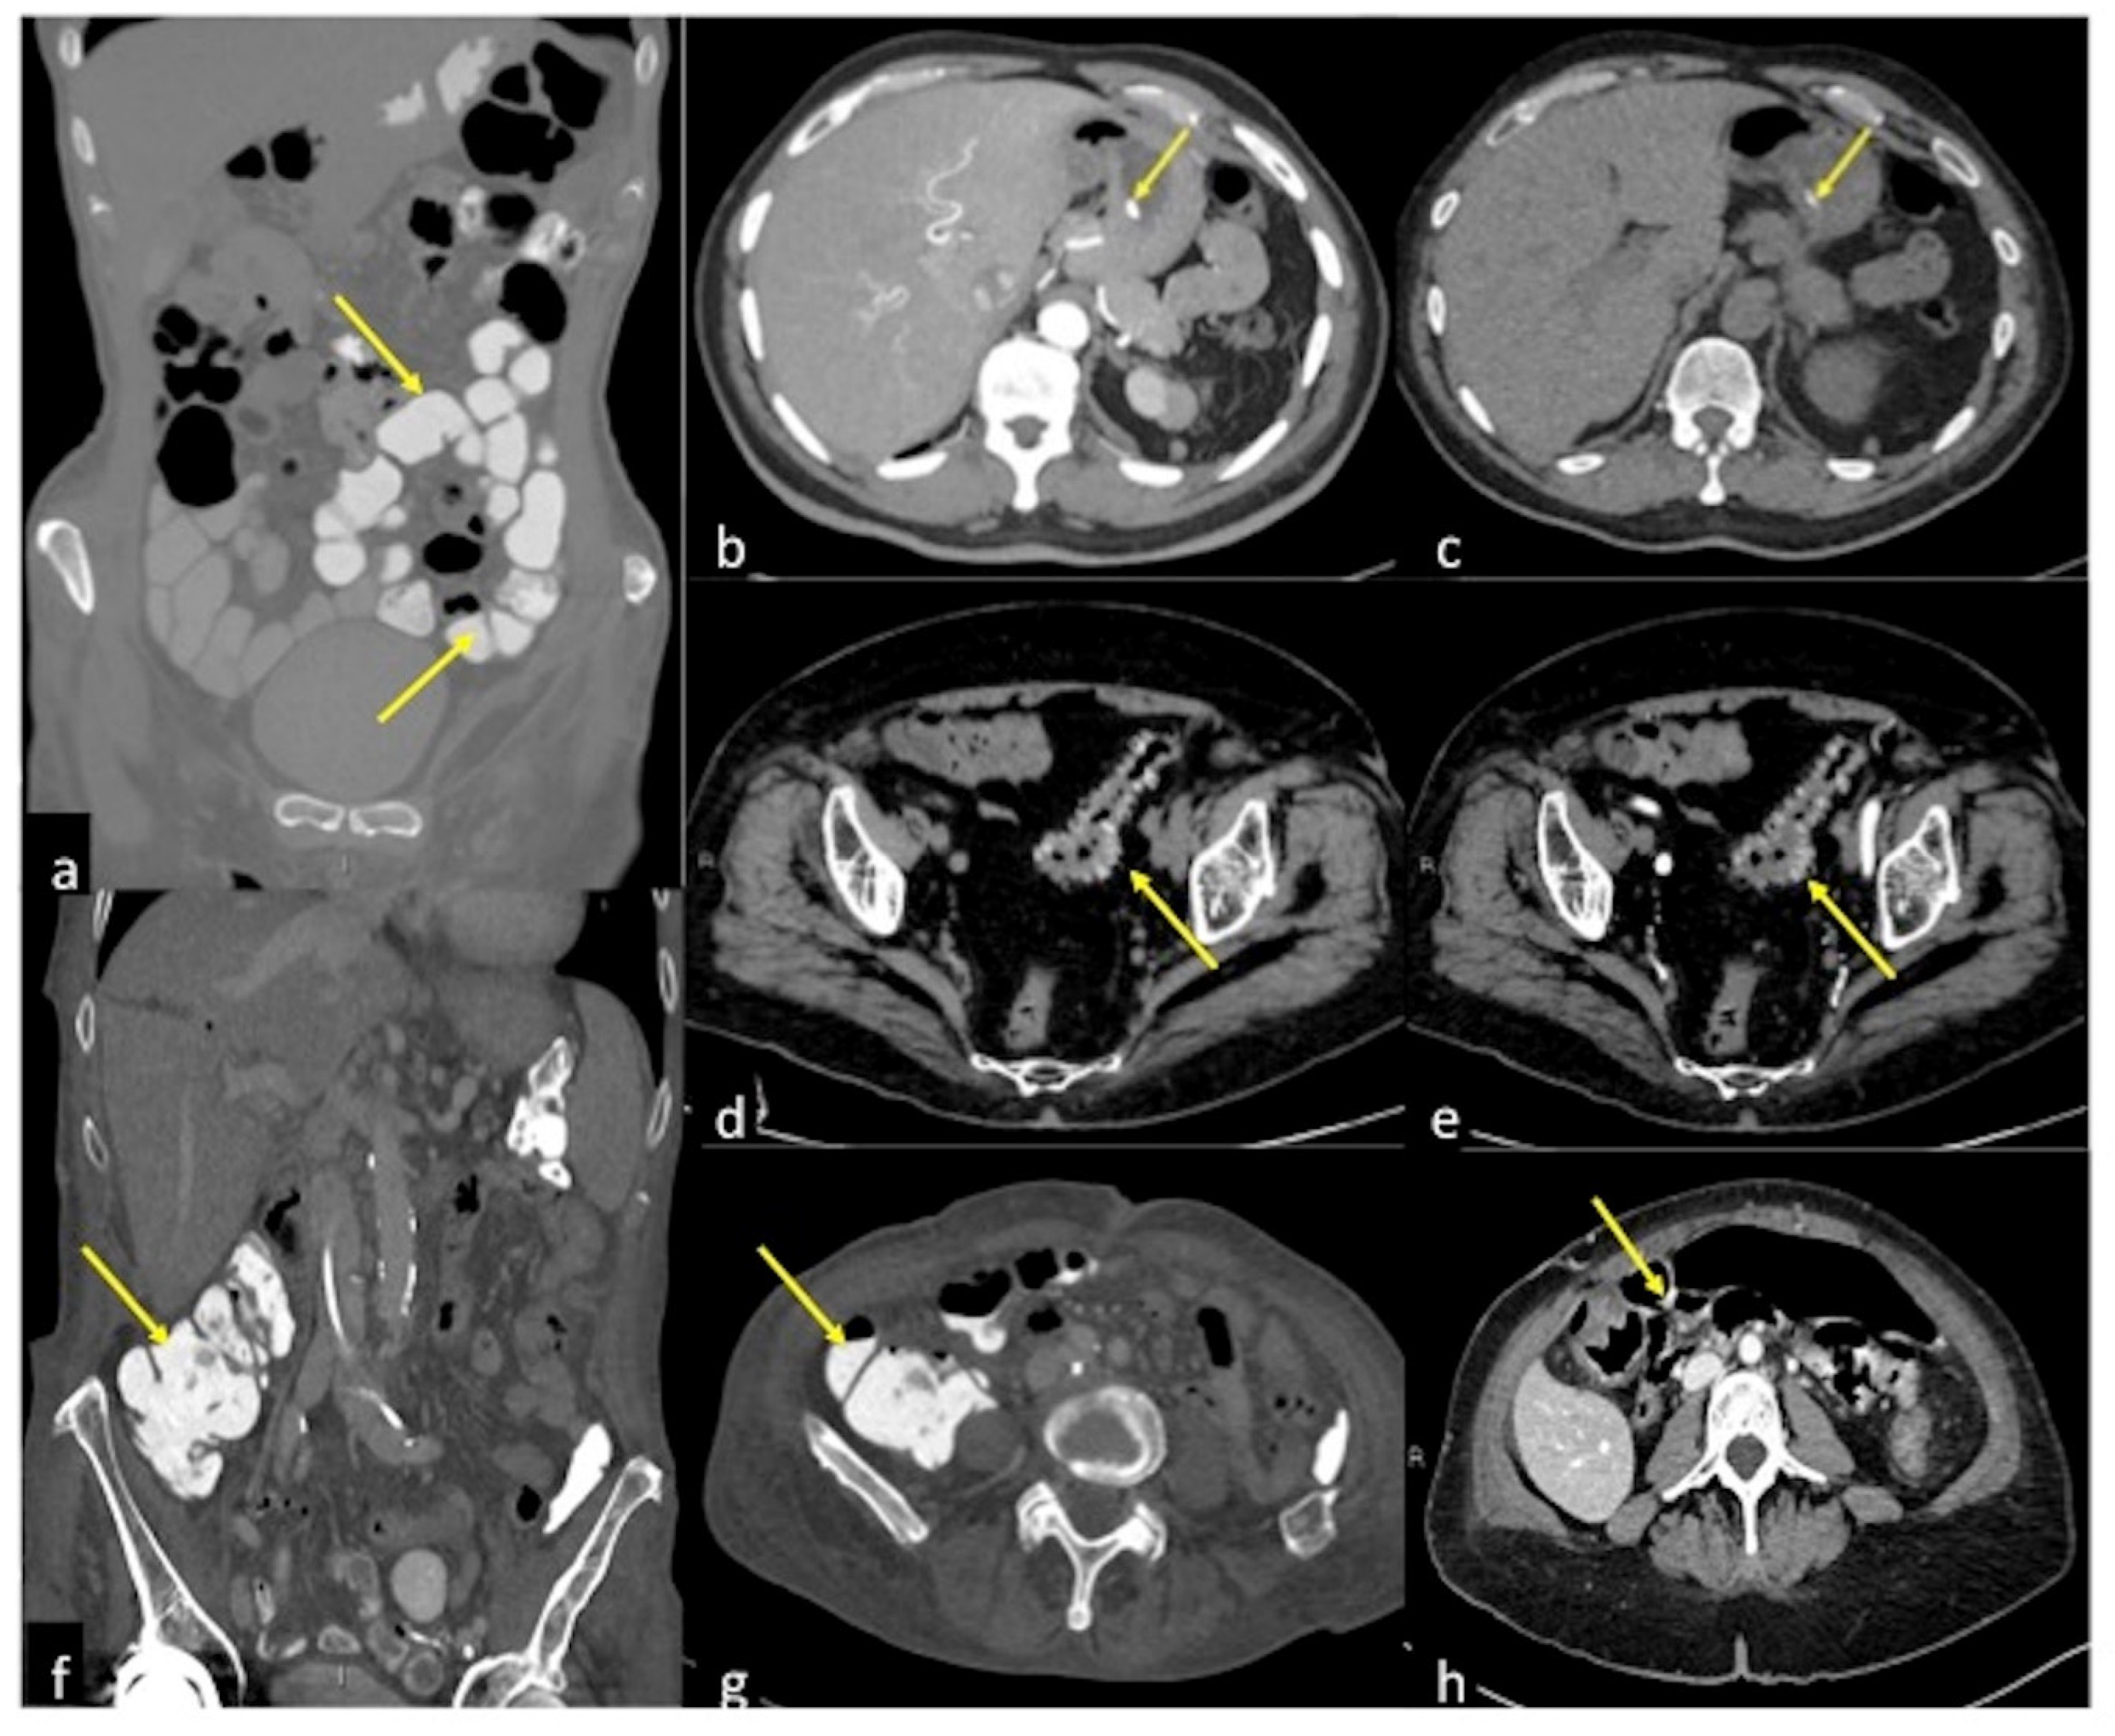

| Meckel’s Diverticulum (Figure 30) | Asymptomatic or, rarely, massive gastrointestinal bleeding. | A diverticulum with fluid or air content originating from the antimesenteric side of the distal ileum. |

| Aorto-Enteric Fistula (Figure 31) | Bleeding in a patient with a history of surgery for aortic aneurysm. | A connection between the aorta and the intestinal lumen. Absence of adipose cleavage planes. |

| Haemobilia (Figure 32) | Melaena, haematemesis, biliary colic, jaundice, or massive bleeding in a patient with a history of blunt or iatrogenic abdominal trauma. | Presence of blood in the gallbladder and biliary tree. |

| Pancreatic Haemorrhage | Intermittent epigastric pain in the abdomen, gastrointestinal bleeding (melaena, haematemesis, haematochezia) and raised serum amylase. | Pseudoaneurysm or pseudocyst with signs of active bleeding, associated with the finding of hyperdense material in the pancreatic ducts. |